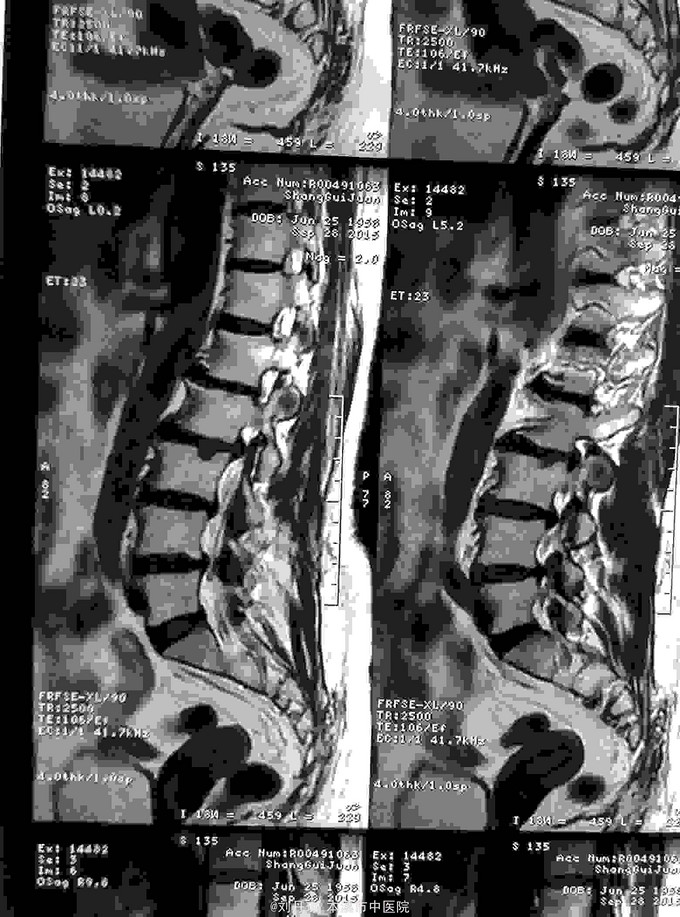

腰部疼痛伴右下肢放射痛麻木感半年,加重2月。患者半年前劳累后感到腰部疼痛伴右下肢放射痛麻木感,近2月病情加重来诊。

查体:L1—S1棘突右旁压痛阳性。直腿抬高实验左70度,右40度。 直腿抬高加强实验左侧阴性,右侧阳性。腰椎功能障碍。 辅查:CT: L1—S1椎间盘突出。

诊断:腰椎间盘突出症 治疗:针灸、雷火灸、中药熏药治疗、小针刀治疗、骶管注射治疗、营养神经药物治疗、脱水药物治疗,当归地黄饮加味。